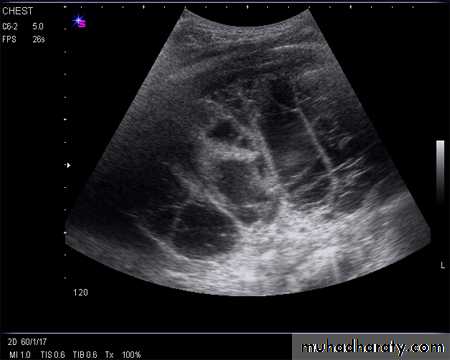

Ultrasound image of heavily septated empyema